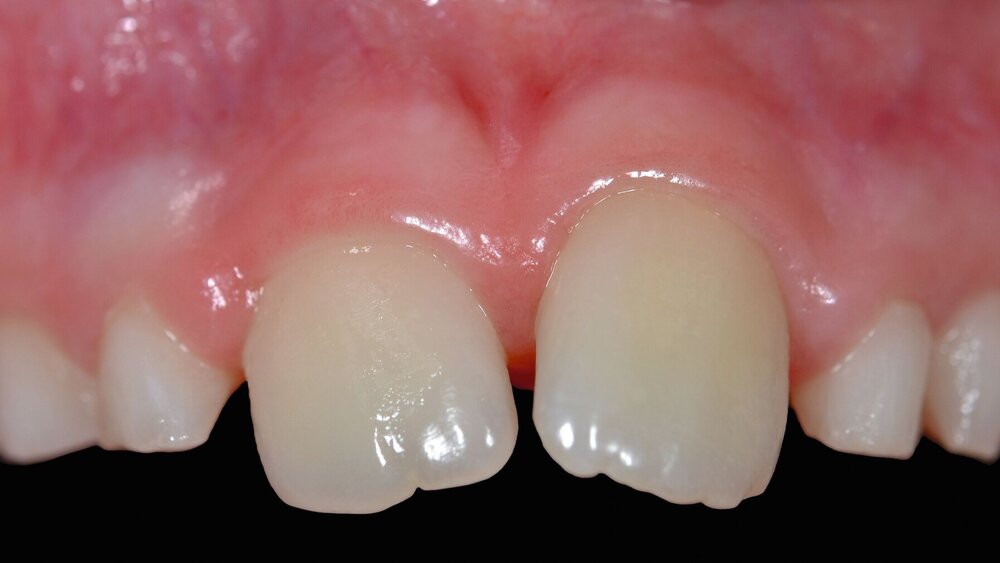

Zum Zeitpunkt des Beratungstermins lagen moderate, reizunabhängige Beschwerden sowie eine deutliche Perkussionsempfindlichkeit und keine Reaktion auf Kälte (— 40°C, Endo Coldspray, Henry Schein, Melville, USA) an Zahn 21 vor. Der horizontale Lockerungsgrad betrug I, die Sondierungstiefen lagen zirkulär bei 2 mm. Klinisch zeigte sich eine ausgeprägte Protrusion des Zahnes 21, die nach Schilderung der Eltern bereits vor dem Unfall vorgelegen hatte (Abbildung 1). Die Zähne 12, 11, 22 und 23 zeigten keine Auffälligkeiten und reagierten plausibel positiv auf Kälte. Zur weiteren Diagnostik wurden eine intraorale Aufnahme der Zähne 12-22 (Abbildung 2a) und eine Aufbissaufnahme (Abbildung 2b) der Frontzahnregion angefertigt. Auf beiden Röntgenbildern war deutlich eine Wurzelquerfraktur an Zahn 21 im mittleren Wurzeldrittel mit Dislokation zu sehen. Zusätzlich war im Vergleich zu Zahn 11 ein Unterschied im Wurzelreifungsgrad erkennbar. Auf Basis der röntgenologischen und der klinischen Befunde musste eine Pulpanekrose mit konsekutiver Entzündung des Parodontiums im Bereich des Bruchspalts als wahrscheinlich angenommen werden.

Nach sechs Monaten erfolgte die klinische und röntgenologische Kontrolluntersuchung. Es lagen klinisch physiologische Schleimhautverhältnisse vor, radiologisch zeigten sich gesunde periapikale Verhältnisse sowie eine intrakanaläre Verschattung im Sinne von appositioniertem Hartgewebe in beiden Fragmenten (Abbildung 7). 30 Monate postoperativ zeigten sich klinisch weiterhin physiologische Verhältnisse (Abbildung 8) mit unauffälligem Klopfschall, radiologisch konnte eine Zunahme der intrakanalären Verschattung im Sinne von Hartgewebe festgestellt werden mit gesunden periapikalen Verhältnissen (Abbildung 9).